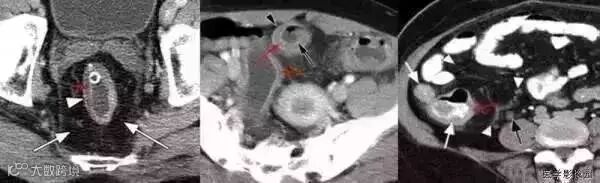

1靶征(肠套叠)

是肠套叠最常见的特征性CT征像,为肠套叠长轴与CT扫描层面垂直时的表现,反映了套叠的各层肠壁、肠腔及肠系膜间的关系。典型排列为自外向内分别代表鞘部外层肠壁、鞘部肠腔内造影剂、鞘部内层肠壁、偏心性套入部肠系膜、套入部肠壁、套入部肠腔内造影剂。

由于肠套叠长轴与CT扫描层面的角度不同,表现各异。如扫描层面和迂曲的肠道相平行时,表现为彗星尾征或肾形征:即套叠近端肠系膜血管牵拉聚拢的征象。一般情况下,彗星尾征均与肾形肿块相伴出现。该肾形肿块为套鞘部游离缘与套入部近端肠管及肠系膜的CT斜切面图像,其中游离的套鞘呈弧形围绕套入部,形状若肾轮廓外形,而套入部近端肠管、肠系膜形状若肾蒂。此时,所谓彗星尾征的组成还应包括套入近端肠管。如果套叠的肠管与CT扫描垂直,则呈靶形征,即肿块影表现为圆形或类似环形。通常在肿块内可分辨出层样结构,推测可能是继发于套入部和鞘部间的液体或是肠壁水肿造成密度对比,类似同心圆形;当套入部肠壁显著水肿坏死或套入部肿瘤周围浸润累及肠系膜,肠系膜血管及脂肪、套叠时间较长,套入部系膜血管受挤压时,静脉血液回流障碍,套入部肠壁充血水肿、变硬,形成不完全性肠梗阻,套叠以上肠管蠕动增强,可引起代偿性肠管扩张肥厚,并可见肠系膜连同其血管纠集、扭曲,形成“漩涡征”。

成人肠套叠还有一些间接征象可帮助诊断,如肠壁不规则增厚或见密度不均匀的软组织块影,伴周围系膜及筋膜浸润、腹膜后淋巴结增大,则提示病因是恶性肿瘤。肿瘤所致肠壁水肿、坏死与部分炎症引起的套叠无法明确区分,肠壁及肠系膜血管有增厚伴肠壁内气体影的征象可提示血运障碍。如CT显示肠套叠直接征象、并伴随近段肠梗阻征象,则表示套入时间较长。如果套入部肠壁及鞘部组织发生水肿、变硬,形成不完全性肠梗阻,套叠以上肠管蠕动增强,可引起代偿性肠管扩张肥厚。